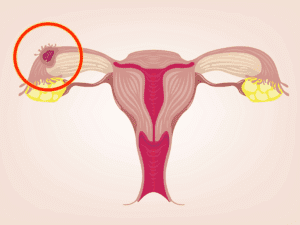

Dış Gebelik Nedir?

Her hamile adayı kadınlarda görülme riski olan bu süreç hamileliğin sağlık bir şekilde tamamlanamaması durumudur. Hamilelikte bazı süreçlerde ortaya çıkan bu durum hayati sağlık sorunlarına neden olacaktır. Döllenmiş yumurtanın rahimde doğru bir şekilde yerleşememesi yahut rahim dışında başka yere yerleşen bu embriyo dış gebeliğe neden olur. Ne yazık ki bu durumda oluşan bir gebeliğin devam etmesi söz konusu değildir. Hamile kadın adaylarının hayatları bile söz konusu olmaktadır. Bu yüzdendir ki dış gebeliğin bir an önce tanı koyulup hemen sonlandırılması gereklidir. Sevindirici bir yanı ise gebeliklerde nadir görülen bir durumdur.” Dış gebelik belirtileri nelerdir ? ” sorusuna cevap aramalı ve bir an önce dış gebelik belirtilerine sahipseniz ivedilikle doktora görünmelisiniz.

Gebeliğin başlangıç sürecinde “ dış gebelik belirtileri nelerdir ? ” gibi sorular yöneltmek sizin lehinize olacaktır. Erken tanı konulamayan bir dış gebelik, yanlı yere yerleşip büyüyen embriyonun fallop tüplerini yırtmasıyla sonuçlanır. Bu durumdan kaynaklan kan ise karın ve pelvis bölgelerinizde ağrılara neden olmaktadır. Siz siz olun küçük bir belirti ortaya çıkmadan bile gebelik öncesi ve gebelik sürecinde doktora görünmeyi ihmal etmeyin.